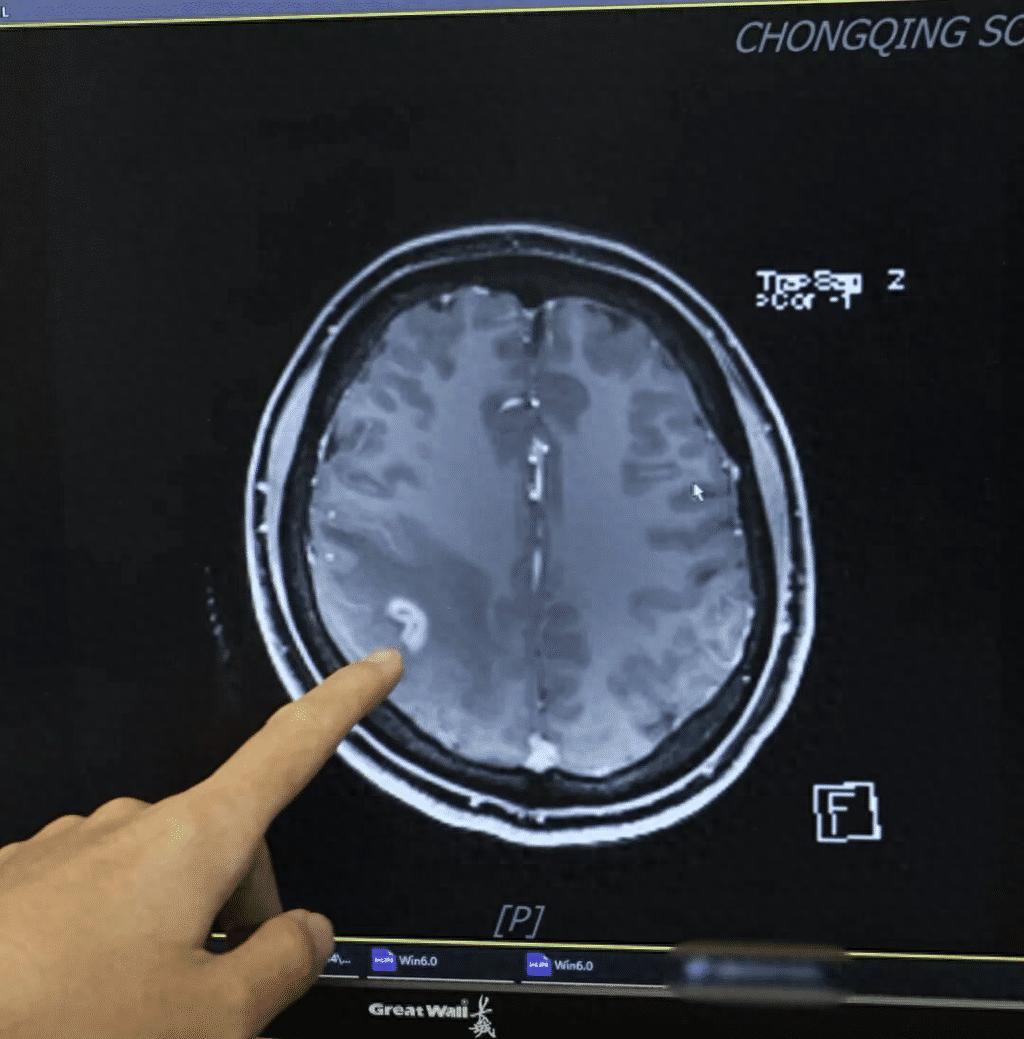

女子做微创手术脑死亡离世,医疗事故不应仅被视为“负面事件”

快评丨女子做微创手术脑死亡离世,医疗事故不应仅被视为“负面事件” 据新京报报道,9月4日,佛山陆先生告诉记者,2024年10月,他妻子在佛山第一人民医院做微创手术,术后因并发症没了自主呼吸,瞳孔放大,被鉴定为脑